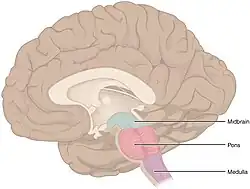

O tronco encefálico, semelhante a um talo, se fixa e deixa o cérebro no início da área do mesencéfalo. O tronco cerebral inclui o mesencéfalo, a ponte e o bulbo raquidiano. Atrás do tronco cerebral está o cerebelo (latim para pequeno cérebro).[6]

Tronco cerebral

O tronco cerebral fica abaixo do cérebro e consiste no mesencéfalo, ponte e medula. Situa-se na parte posterior do crânio, repousando na parte da base conhecida como clívo, e termina no forame magno, uma grande abertura no osso occipital. O tronco cerebral continua abaixo dele como a medula espinhal, protegida pela coluna vertebral.[36]

Dez dos doze pares de nervos cranianos emergem diretamente do tronco cerebral.[36][36] O tronco cerebral também contém muitos núcleos de nervos cranianos e de nervos periféricos, bem como núcleos envolvidos na regulação de muitos processos essenciais, incluindo respiração, controle dos movimentos oculares e equilíbrio.[37][36] A formação reticular, uma rede de núcleos de formação mal definida, está presente dentro e ao longo do tronco cerebral.[36] Muitos tratos nervosos, que transmitem informações de e para o córtex cerebral para o resto do corpo, passam pelo tronco cerebral.[36]